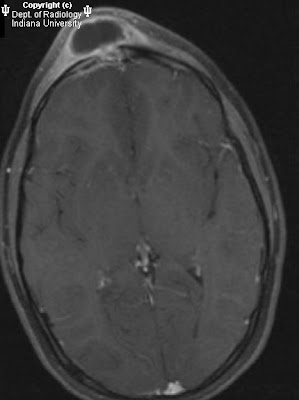

Findings

There is loculated fluid within the right frontal sinus with thick, nodular peripheral enhancement. This is associated with cortical disruption of both the outer and inner table table of the right frontal bone. There is mild thickening and asymmetric enhancement of the subjacent dura without discrete intracranial fluid collection is seen. Extracranially the right frontal sinus is contiguous with a scalp fluid collection, also demonstrating peripheral enhancement with mild induration in the adjacent subcutaneous tissues.

Diagnosis: Pott’s puffy tumor (frontal sinusitis, osteomyelitis, abscess)

Frontal sinus opacification, destruction of inner and/or outer table of bone, soft tissue mass/fluid collection (abscess) in scalp tissues or in extra-axial space.

MRI:

- T2: Sinus hyperintensity.

- T1: Disruption of inner/outer tables of frontal bone.

- T1+C:

Rim-enhancing fluid collection in superficial scalp.

Key in characterizing intracranial involvement, i.e., underlying dural enhancement / enhancing extra-axial collection.